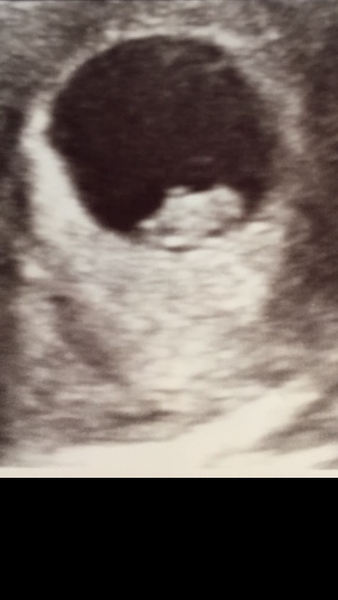

Mooseville · 22/10/2016 07:45

Morning everyone,

It's lovely to read all your baby news and I'm picking up some good tips already from you ladies! Lara that birth story sounded lovely. It's so nice to hear one that doesn't sound scary!

I had a viability scan yesterday and there was a lovely blob there with a little flickering heartbeat all doing what it was meant to! It's definitely feeling more real now!!!

Woohoo on the heartbeat moose!

Fab scan moose!

Ooooh moose that's your little bean! How lovely! Enjoy every minute of being pregnant (if possible) cause I've found it flies by in the blink of an eye! Congratulations!

Lovely scan moose so many more lovely scans to come, too! Grin